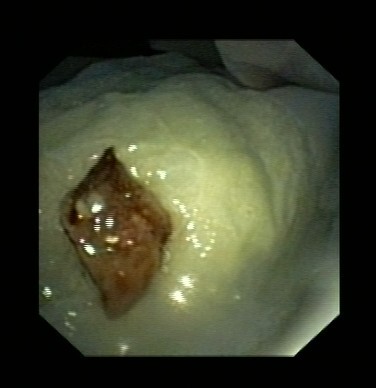

近日,吕先生有门诊收入我呼吸科住院治疗,全体医护人员高度重视,认真讨论病情。我科吴主任仔细看过吕先生的CT片后,观察到右下肺气管内异物,于是决定行支气管镜检查。在气管镜室,吴主任给他做了支气管镜检查,发现吕先生右下肺支气管内卡着一个黑黑的异物,由于时间太久,异物周围已充血水肿,表面有脓苔及坏死物覆盖,清除脓苔及坏死物后,可见异物被肉芽组织紧紧包埋。吴主任成功取出了吕先生气管内异物,并吸出了气管内脓性分泌物。吕先生咳嗽症状立刻改善,行气管镜检查后第二天患者无咳嗽症状,顺利出院。

图表3取出异物后气管周围肉芽组织